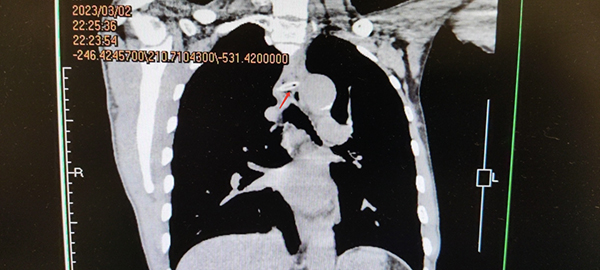

胸部CT照片(红色箭头指向异物处)

了解情况后,消化内镜中心副主任何玉琦翻阅了患者的胸部CT,决定先用胃镜检查一探究竟。结果这不查不知道,一查之后真吓一跳,整个牛骨头横跨在食管腔内,把食管堵了个严严实实,而且两端非常锐利垂直穿入食管两侧壁内,极有可能存在食管穿孔。